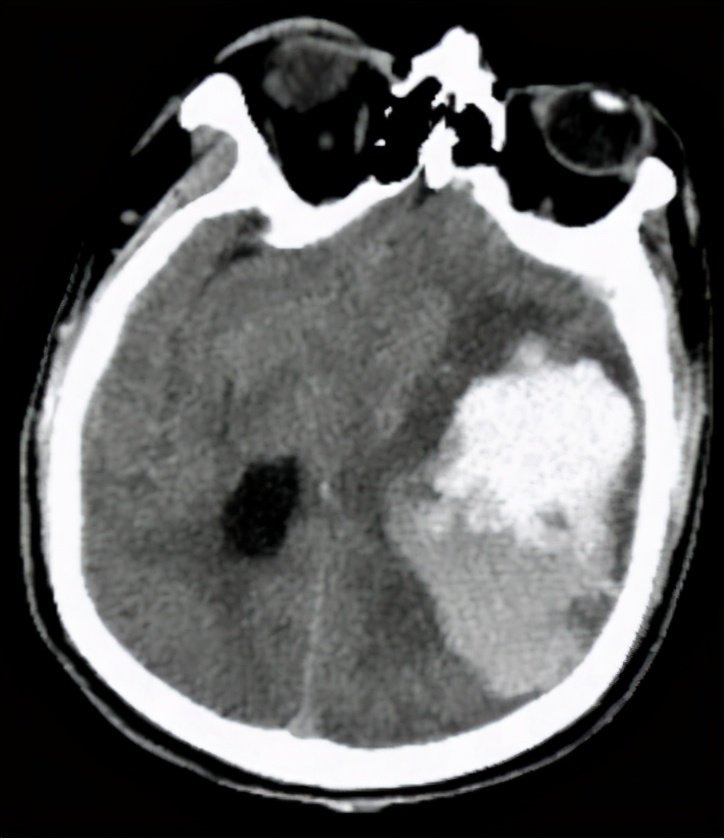

患者老年女性,63岁,既往高血压十年,偶尔服药治疗。一周前突然神志不清2小时,被紧急送到了湘南学院附属医院救治。入院检查,血压195/95 mmHg,头部CT示左侧基底节区脑出血。

神经外科罗忠平主任详细研究了患者资料,指出:颅内出血量大,神志昏迷,脑室中线受压明显,脑疝形成,有明确手术指征。决定行大骨瓣开颅+去骨瓣减压术。

术前